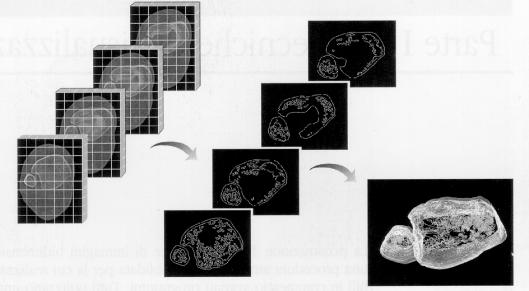

La  figura 1‑7 mostra un filtraggio  per il rilevamento e l’evidenziazione dei contorni.

Figura 17 Filtraggio di tipo find-edges enhanced